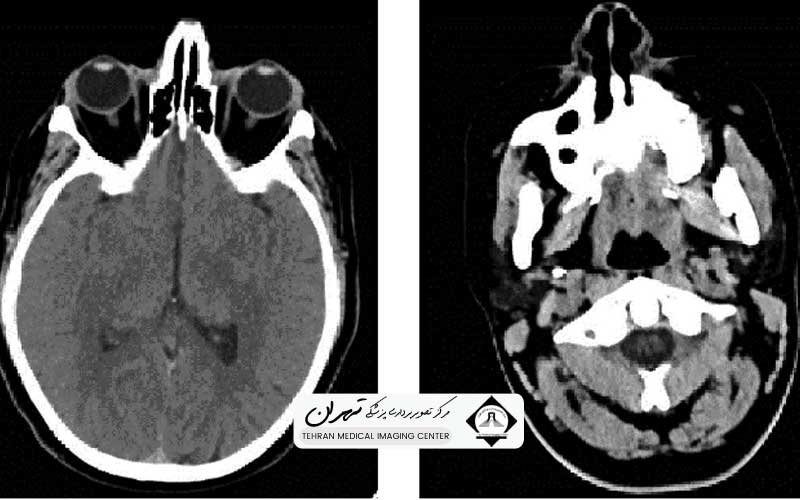

در بررسی علمی عکس سی تی اسکن مغز سالم، ما با مفاهیمی فراتر از یک عکس سیاه و سفید روبرو هستیم. ما با “واحدهای هانسفیلد” (Hounsfield Units) سر و کار داریم که میزان جذب اشعه ایکس توسط بافتهای مختلف را نشان میدهند. در یک مغز سالم، تفکیک ظریف میان ماده خاکستری (Gray Matter) و ماده سفید (White Matter)، وضعیت بطنهای مغزی، باز بودن سیسترنها و عدم وجود شیفت میدلاین (Midline Shift)، همگی نشانگرهایی هستند که سلامت سیستم عصبی مرکزی را تایید میکنند. شناخت این الگوهای نرمال برای دانشجویان پزشکی، رزیدنتها و حتی بیمارانی که به دنبال درک گزارش تصویربرداری خود هستند، بسیار حائز اهمیت است.

برای درک عمیق عکس سی تی اسکن مغز سالم، ابتدا باید زبان دستگاه سیتیاسکن را بیاموزیم. این زبان، زبان “دانسیته” یا چگالی است. دستگاه سیتیاسکن با ارسال پرتوهای ایکس از زوایای مختلف و پردازش کامپیوتری میزان جذب این پرتوها، تصویری ماتریسی میسازد. معیار سنجش این چگالی، واحد هانسفیلد (HU) است.

در یک اسکن مغز سالم، هر بافت عدد هانسفیلد مشخصی دارد:

- استخوان جمجمه: به دلیل تراکم کلسیم بالا، بیشترین جذب اشعه را دارد و به رنگ کاملاً سفید (Hyperdense) دیده میشود. عدد هانسفیلد آن معمولاً بالای ۱۰۰۰+ است.

- هوا: کمترین جذب را دارد و در سینوسهای پارانازال و سلولهای هوایی ماستوئید به رنگ کاملاً سیاه (Hypodense) دیده میشود. عدد هانسفیلد آن حدود ۱۰۰۰- است.

- مایع مغزی-نخاعی (CSF): مایعی که درون بطنها و فضای سابآراکنوئید جریان دارد، دانسیتهای نزدیک به آب دارد (حدود ۰ تا ۱۵ HU) و در تصویر به رنگ سیاه (اما نه به سیاهی هوا) دیده میشود.

- بافت مغز: نکته کلیدی در تشخیص سی تی اسکن مغز سالم، تفکیک بافت مغز است. ماده سفید مغز (شامل اکسونهای میلیندار) به دلیل محتوای چربی بالاتر، کمی تیرهتر از ماده خاکستری دیده میشود (حدود ۲۰ تا ۳۰ HU). در مقابل، ماده خاکستری (شامل اجسام سلولی نورونها) کمی روشنتر است (حدود ۳۵ تا ۴۵ HU).

حفظ این کنتراست ظریف بین ماده سفید و خاکستری بسیار حیاتی است. در شرایطی مانند سکته مغزی ایسکمیک (CVA) یا ادم مغزی، این تمایز از بین میرود و بافتها اصطلاحاً “محو” میشوند. بنابراین، در یک عکس سالم، شما باید بتوانید مرزهای شکنجها (Gyri) و شیارها (Sulci) را تا حد خوبی تشخیص دهید. هرگونه تغییر در این اعداد هانسفیلد، مثلاً وجود لکههای سفید در بافت مغز (که میتواند نشاندهنده خونریزی یا کلسیفیکاسیون باشد) یا لکههای سیاه غیرعادی (نشاندهنده کیست، تومور یا سکته قدیمی)، الگوی سالم را برهم میزند.